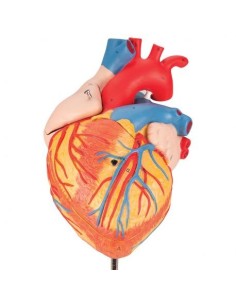

Du crâne en 22 parties à verrouillage magnétique aux modèles de colonne vertébrale, des modèles d'articulation aux modèles de cœur, chaque pièce de notre collection est conçue pour une immersion totale dans l'étude de l'anatomie humaine. Nos modèles, réalisés à partir de scans d'os réels, garantissent une expérience tactile authentique et une fidélité de poids presque identique aux originaux.